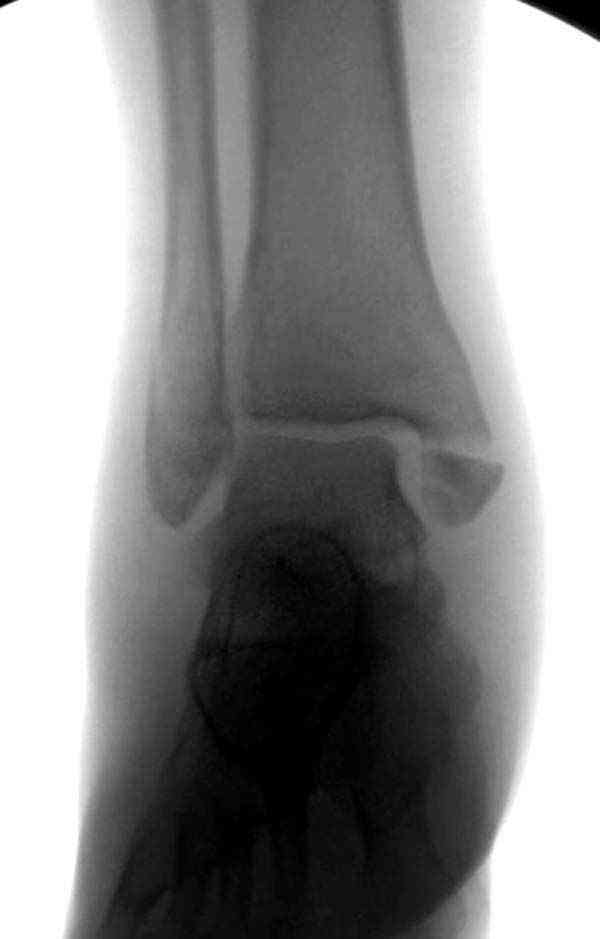

Нет первичных снимков, перелом очень низкий и под большим сомнением диагноз разрыва синдесмоза. Медиальная сторона отрепонирована на "хорошо" и, по-видимому, прорезание проволоки произошло во время операции. Без снимков трудно судить о высоте малоберцовой, а лодыжка находится в варусе. Лагирование получилось, но возле тонких шурупов передне-задний шуруп выглядит немного тяжеловато.

Здесь несколько частных случаев: перелом голеностопа со сравнительными снимками и разрыв синдесмоза, а также медиальная Hook пластина.